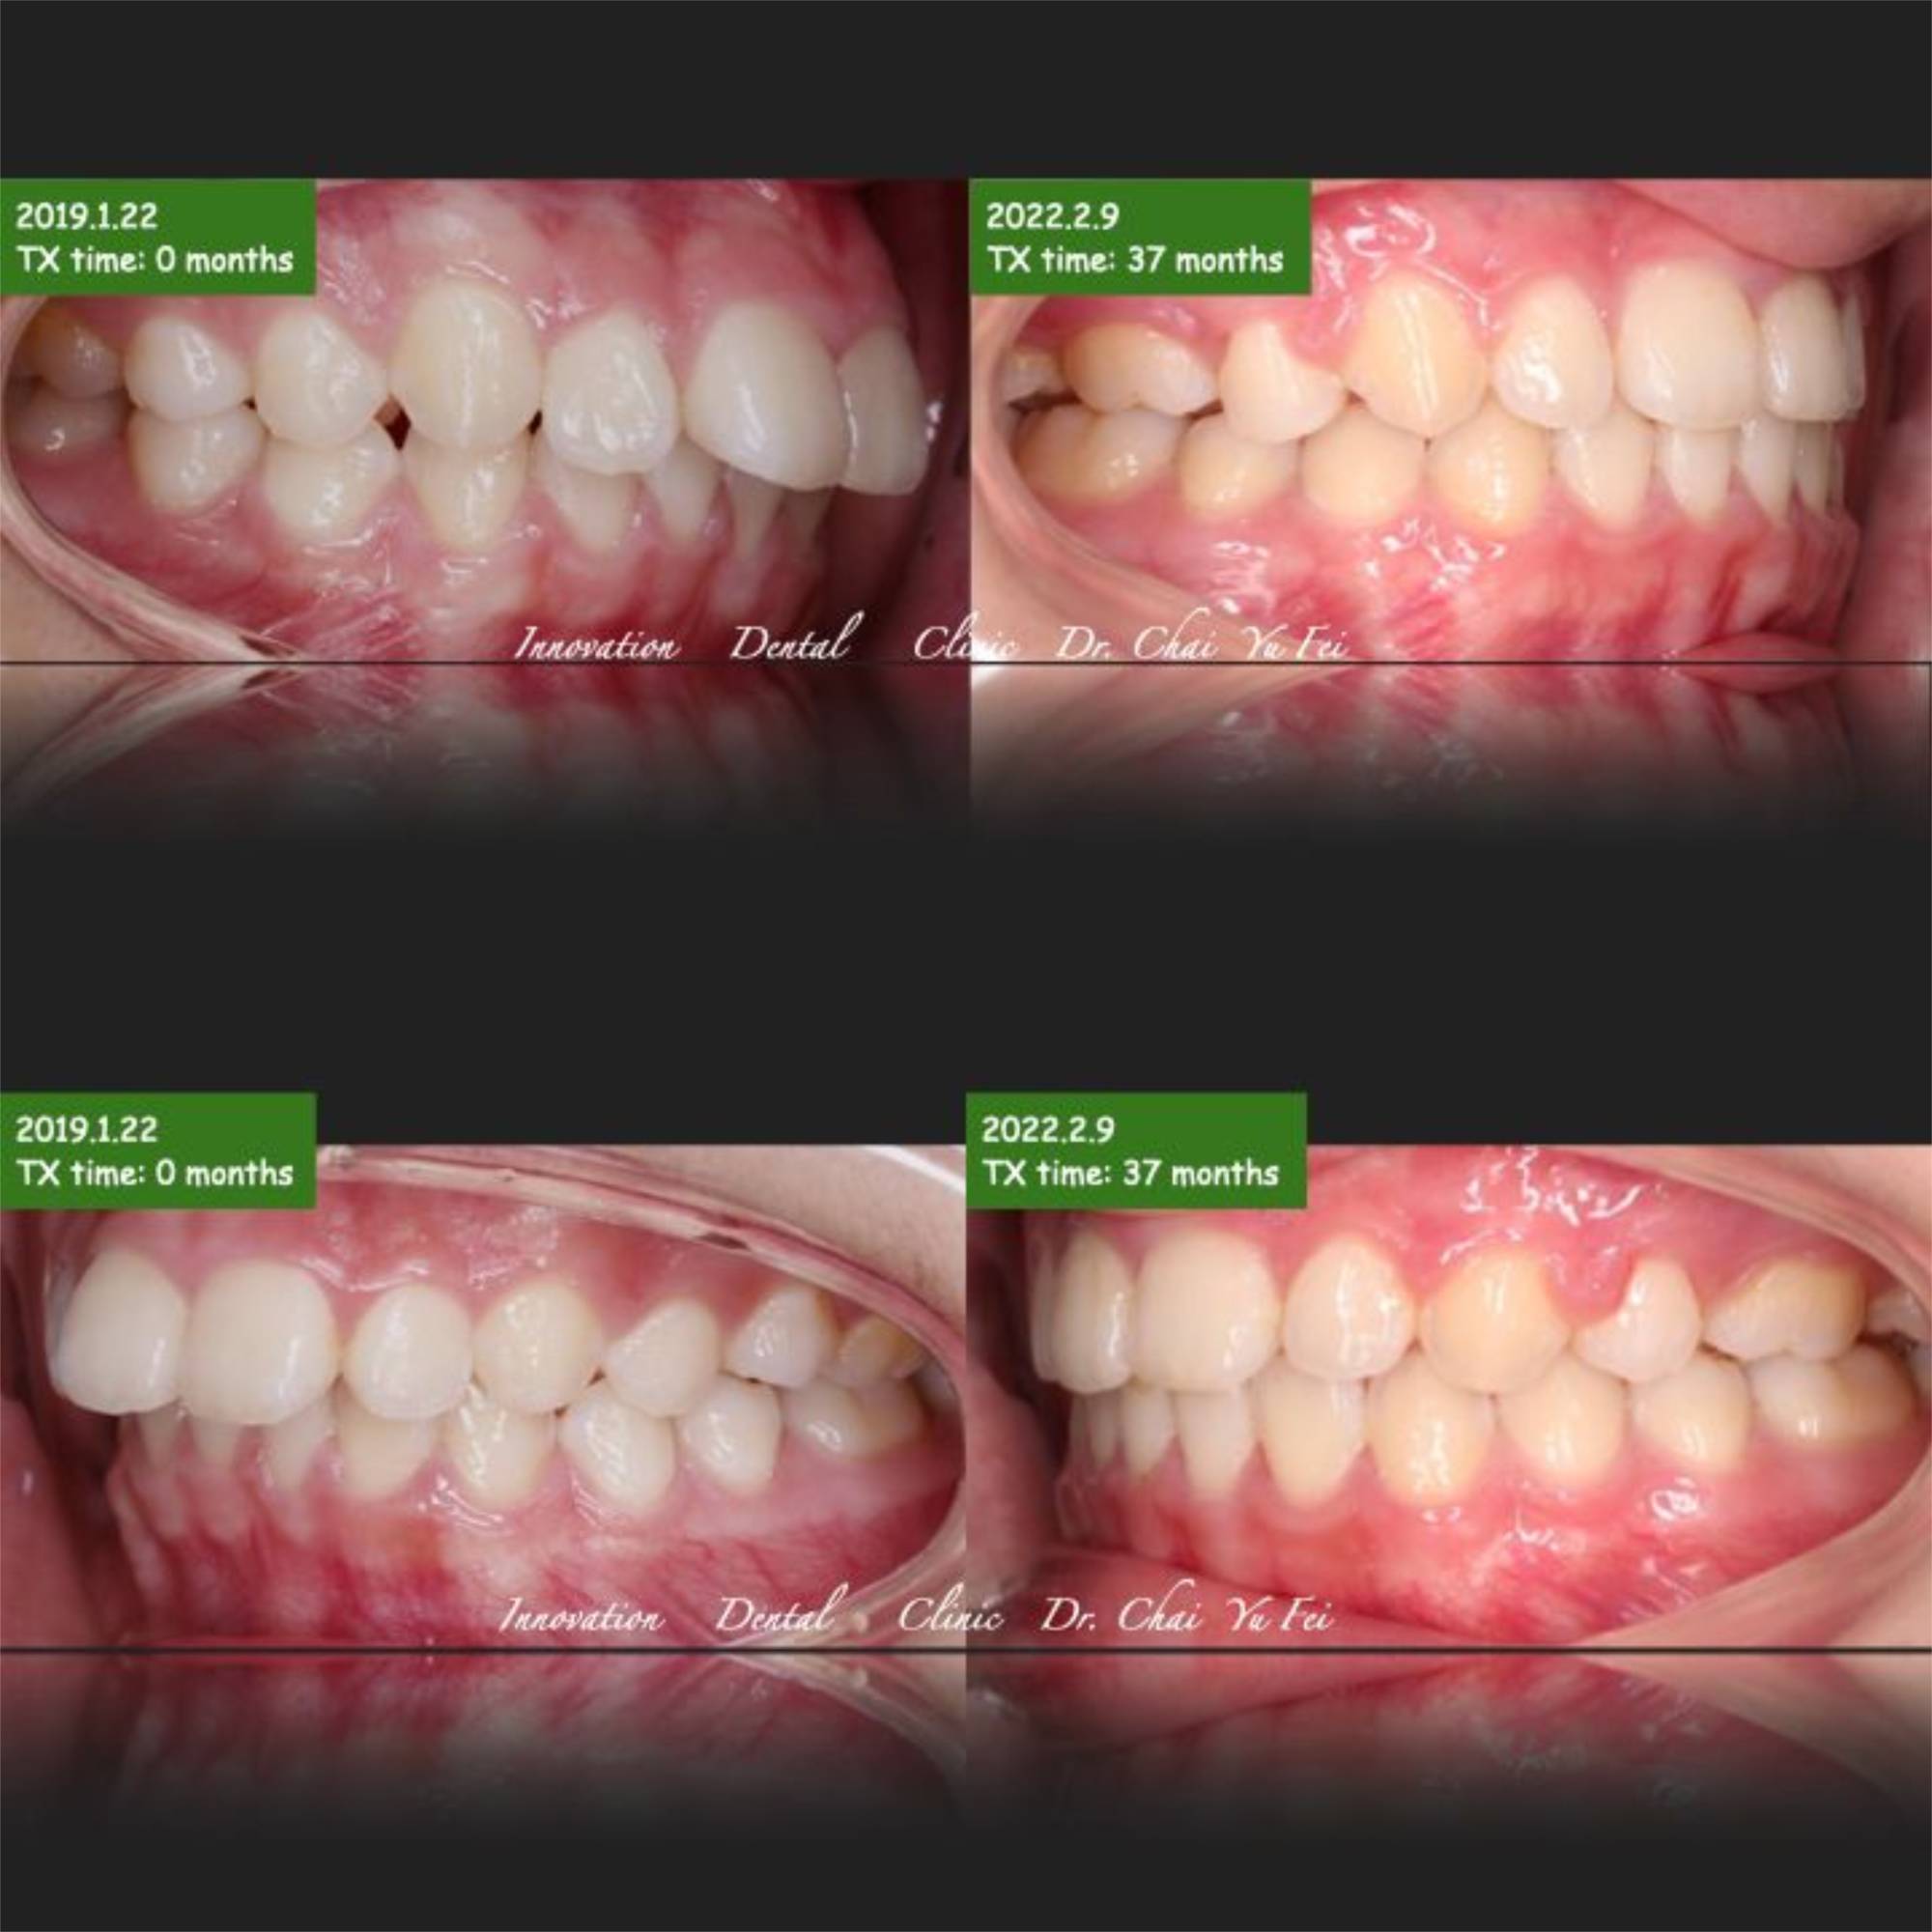

果然,在翟醫師的治療之下,患者原本前凸跟狹窄的上顎齒列,藉由上顎2顆小臼齒移除之後,暴牙的感覺完全消失,下顎也伴隨她的生長發育跟橡皮筋進行的下顎牽引,我們得到了一個很好的輪廓~最後的成果讓人很感動。

上顎暴牙矯正前後變化,改善露牙齦外觀

最後分享邱同學的矯正成果給大家參考:

矯正牙齒不只是醫生的功勞,很感謝邱同學在矯正期間的配合,中間經歷疫情好幾個月沒有回診調整,還是有認真清潔保養,最後很幸運完成在這樣的狀態~